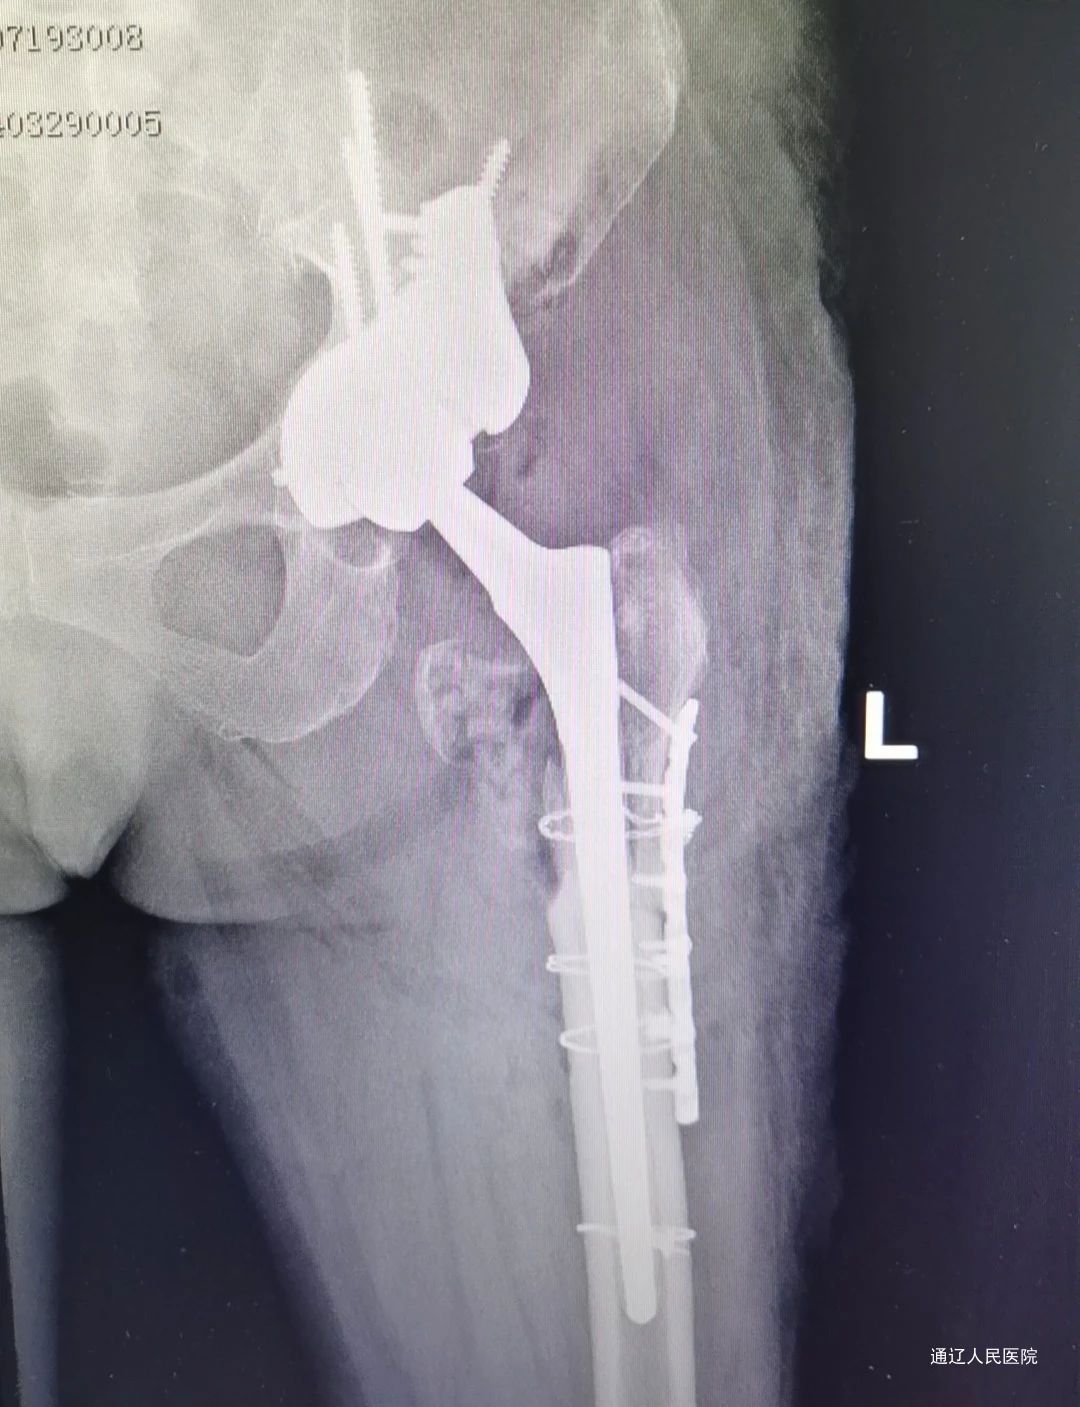

术后X线检查